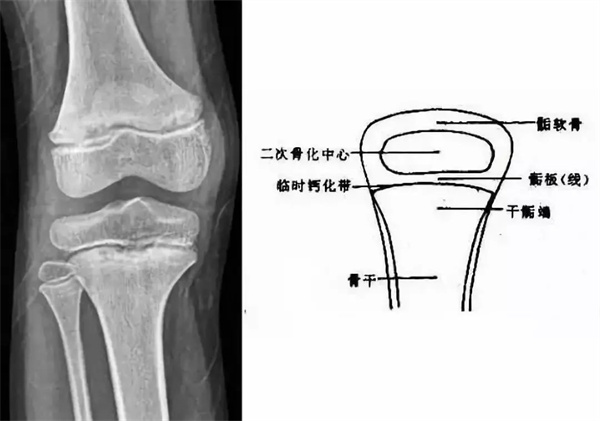

我們都知道,人體的高矮是由骨骼的生長發(fā)育決定的,特別是下肢長骨。長骨呈長管狀,在長骨的兩端有一種專管骨骼生長的骺軟骨,它與干骺端之間有一盤狀軟骨結(jié)構(gòu)稱為骺板(線),在幼兒的X光片上表現(xiàn)為一條較寬的透光帶。(見下圖)

未成年時隨著年齡的增加骺軟骨端不斷骨化,骨骼就不斷增長。當(dāng)骨骺線完全閉合時骨骼就停止生長,個子也就不再增長了。一般骨骺端完全閉合的年齡是18~20歲左右。